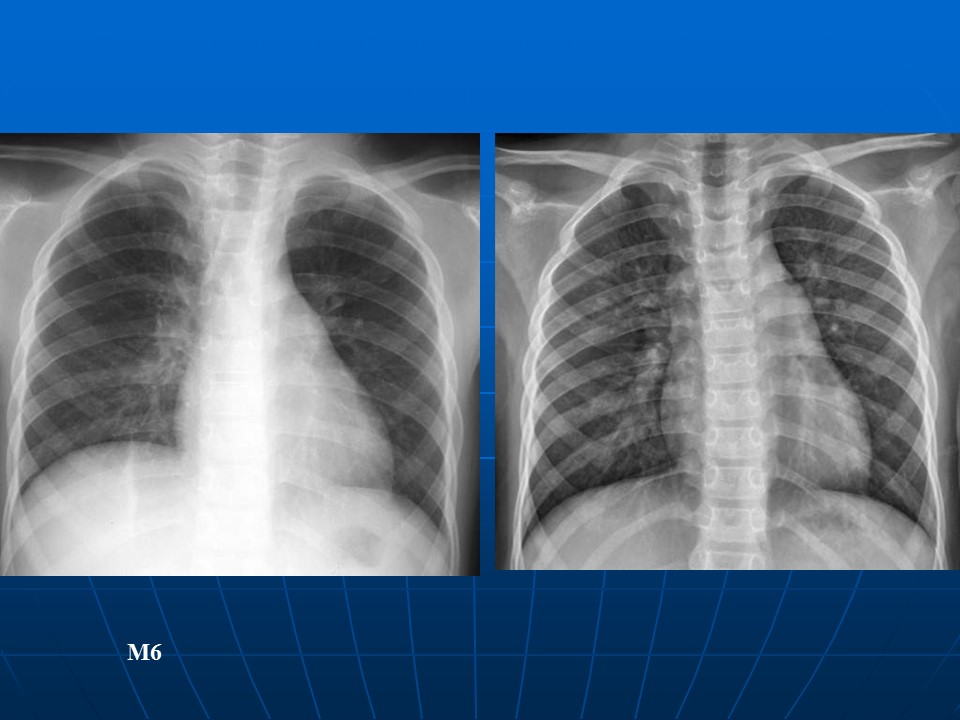

如何在影像上判断新冠病毒肺部感染是否好转